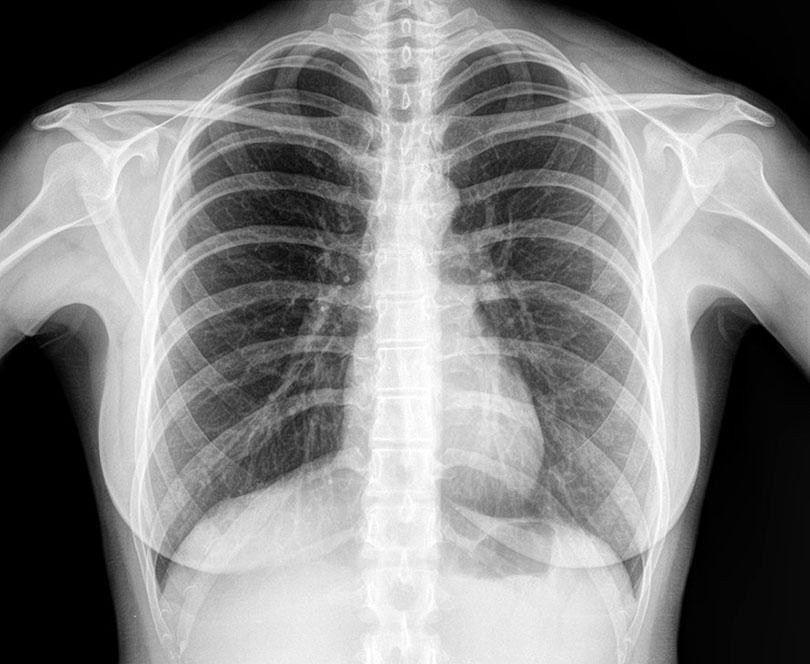

In 2010, a Brooklyn woman called Lavern Wilkinson went to the Kings County Hospital due to chest pain. An X-ray was taken, and she was sent home by a first-year resident who said she was fine. Unfortunately, she began to experience breathing problems shortly after that and was diagnosed with asthma. When she still had no relief, and the problem worsened, Lavern went back to the hospital in 2012 and received devastating news.

When a doctor looked at the X-ray that had been taken two years earlier, they saw that the first-year resident had missed a small mass visible on the X-ray, which would have been curable at the time. However, because the mass was missed, Lavern had developed full-blown lung cancer in the two years following that fateful visit. Worse, the cancer spread to her other organs by 2013, and she died later that year at the age of 41.